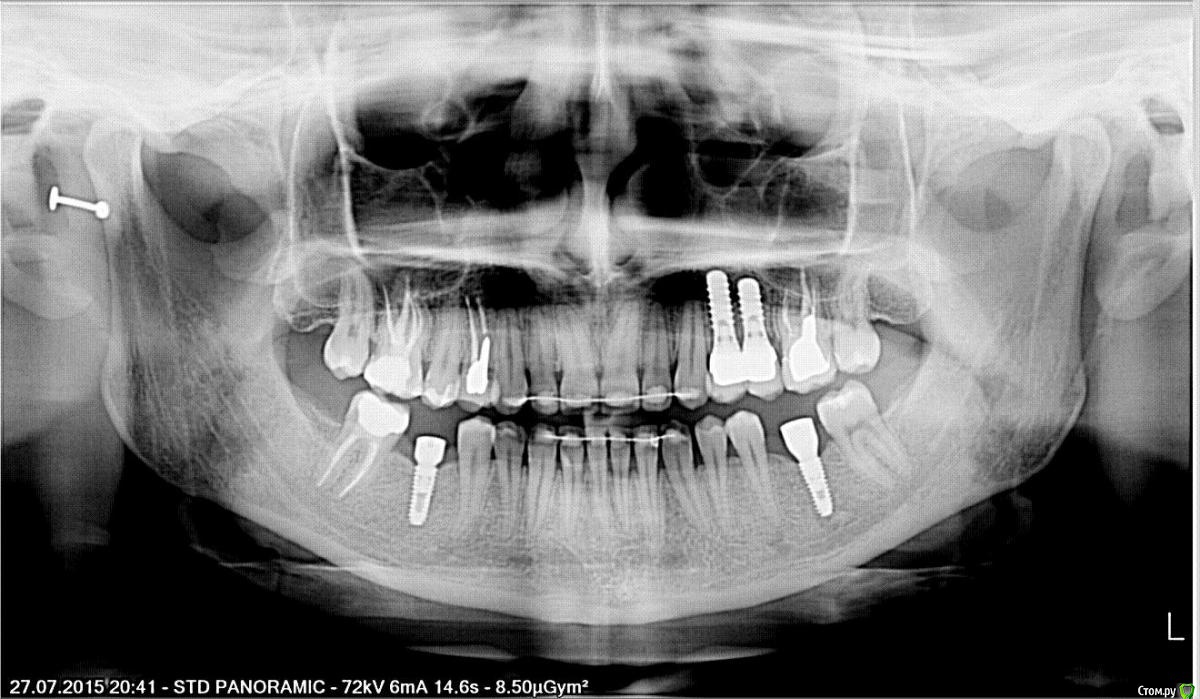

Тая.А Опубликовано 7 августа, 2015 Поделиться Опубликовано 7 августа, 2015 Здравствуйте, Есть вопросы по зубу (если не ошибаюсь, то 6-му.Тот, что рядом с двумя имплантатами, вкладка металлическая, коронка безметалл.) 1.На снимке есть белая маленькая полосочка со стороны имплантатов, если это цемент, он может как-то сильно дурно отразиться на жизни зуба, запахи, проникновение микробов например? 2.Раньше на этом зубе была металлокерамика, но раздражала гирлянда и вообще присутствие металла во рту.Сейчас безметалл, выглядит получше, но за счет того, что десна в том месте уже не так плотно прилегает к зубу, то зубочисткой, немного под десной, я могу нащупать стык коронки и шейки зуба (та часть, которая не затронута вкладкой). При использовании ирригатора и хорошей гигиене туда ничего из пищи не проникнет, что вызовет запахи и пр.? Да простят меня все врачи за мое занудство и беспокойство. Ссылка на комментарий

red_butler Опубликовано 8 августа, 2015 Поделиться Опубликовано 8 августа, 2015 1.На снимке есть белая маленькая полосочка со стороны имплантатов, если это цемент, он может как-то сильно дурно отразиться на жизни зуба, запахи, проникновение микробов например? ничего страшного не увидел то зубочисткой забудьте о зубочистках, как о страшном сне и просто покажитесь своему ортопеду Ссылка на комментарий